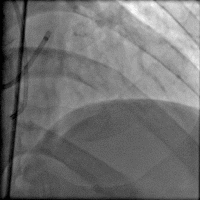

冠脉造影

造影时间: 入院当天03:35~03:52。

造影结果(一): 前降支近段闭塞,回旋支中远段90%狭窄。

造影结果(二): 右冠中段闭塞。

造影结论及应对策略: 前降支近段闭塞,回旋支中远段90%狭窄,右冠中段闭塞,未行左室造影。病变血管:前降支;回旋支;右冠。与家属沟通,同意行PCI。